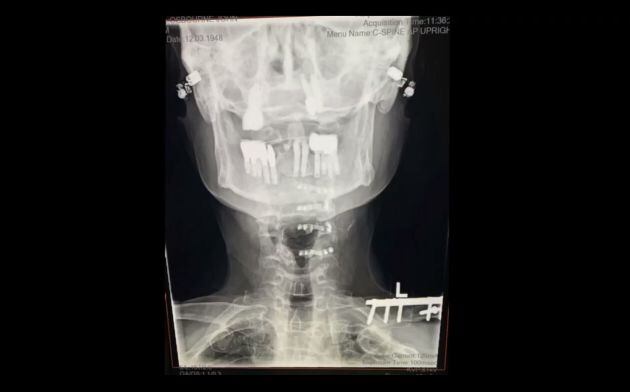

"A principios de año tuve una mala caída y necesité cirugía. Ahora tengo más tuercas y tornillos en el cuello que en mi coche. No me estoy muriendo, me estoy recuperando, es solo que llevará un poco más de tiempo de lo que todos pensaban", ha dicho Osbourne en el vídeo que ha compartido.

Radiografía del cuello de Ozzy Osbourne tras la instalación de prótesis metálicas. / Ozzy Osbourne